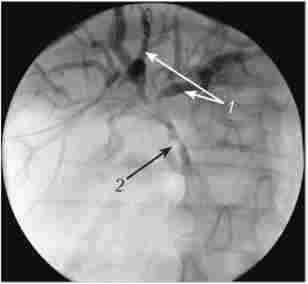

В останні роки, завдяки розвитку медичної техніки, для діагностики захворювань гепатобіліарної зони все ширше застосовуються комп'ютерна томографія (КТ) та магнітно-резонансна холангіопанкреатографія - МРХПГ (рис. 18.4). МРХПГ незамінна в діагностиці причин механічної жовтяниці, так як по інформативності порівнянна з ЕРПХГ і ЧЧХГ, але має важливу перевагу - неінвазивний.

Магнітно-резонансна холангіопанкреатографія

Мал. 18.4. Магнітно-резонансна холангіопанкреатографія.

Видно розширені позапечінкові жовчні протоки, конкременти в холедохе (вказані стрілкою)